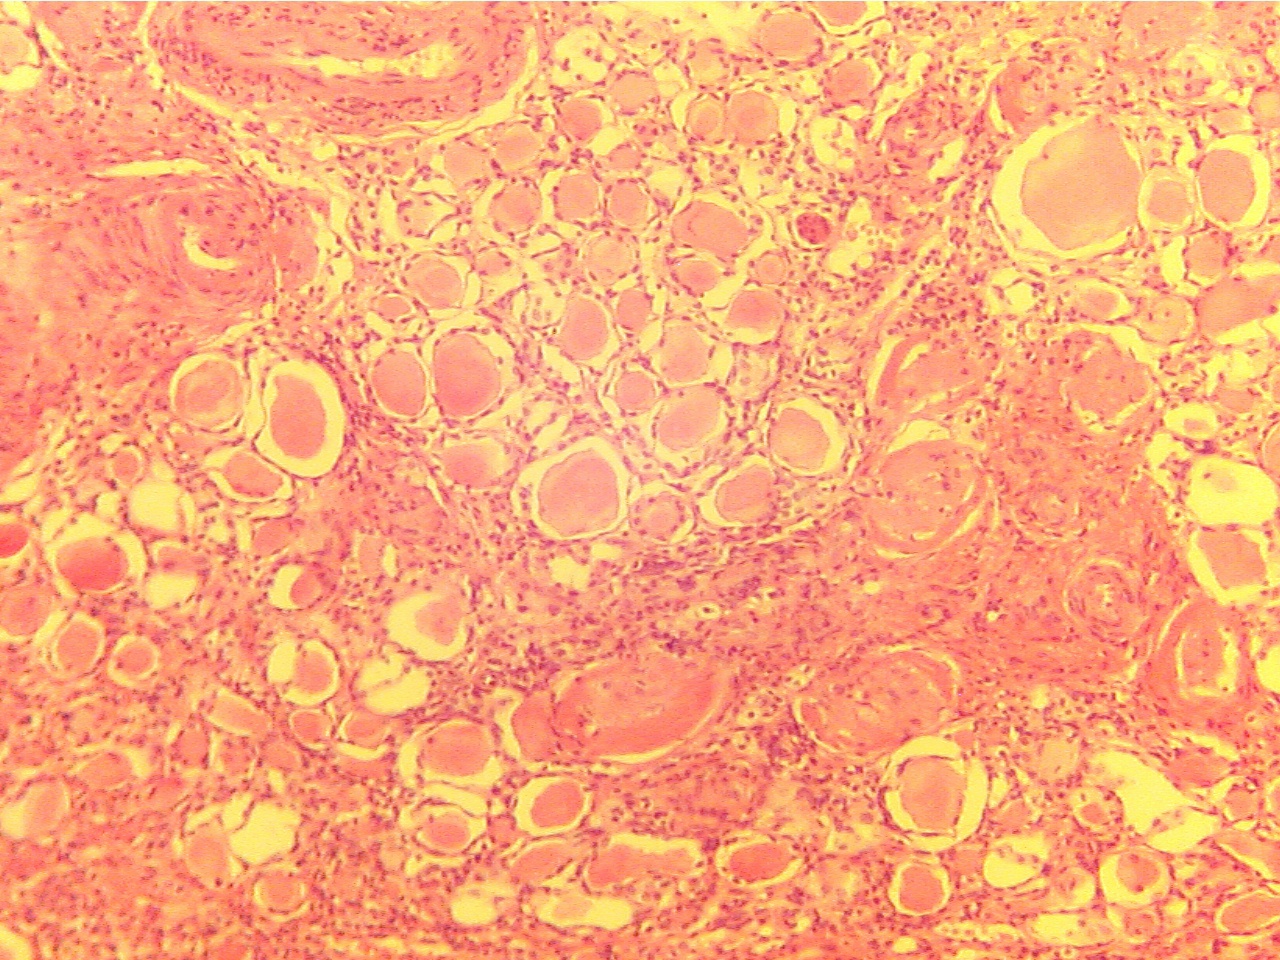

Chronic Pyelonephritis -(Chronic Pyelitis and Pyonephrosis

This slide emphasizes the presence of protein casts in the tubules.

(See Fig. 46-6, p. 700, Fig. 46-11, p. 706). The damaged tubules have leaked

proteins which have coagulated into the round pink casts. (Pyelitis means

the renal pelvis is infected and pyonephrosis means hydronephrosis which

has become infected. You do not have to know these two terms). Do not confuse

casts in tubules with hyalinized glomeruli even though they are similar

in appearance.

Kidney tubules containing casts

(40X2.0)

Kidney tubules containing casts (100X2.0)

Casts are very numerous, are of different sizes, and in these slides,

contain no cells or nuclei.

Hyalinized glomeruli in our slides are fewer in

number, of equal sizes, and contain a few cell nuclei.

The outward pressure from a cast in a tubule

causes atrophy (thinning) of the tubule cells

from their normal cuboidal shape to a thin flat

squamous shape. Inflammation is evident from

the presence of many inflammatory cells (small dark blue)

between the tubules